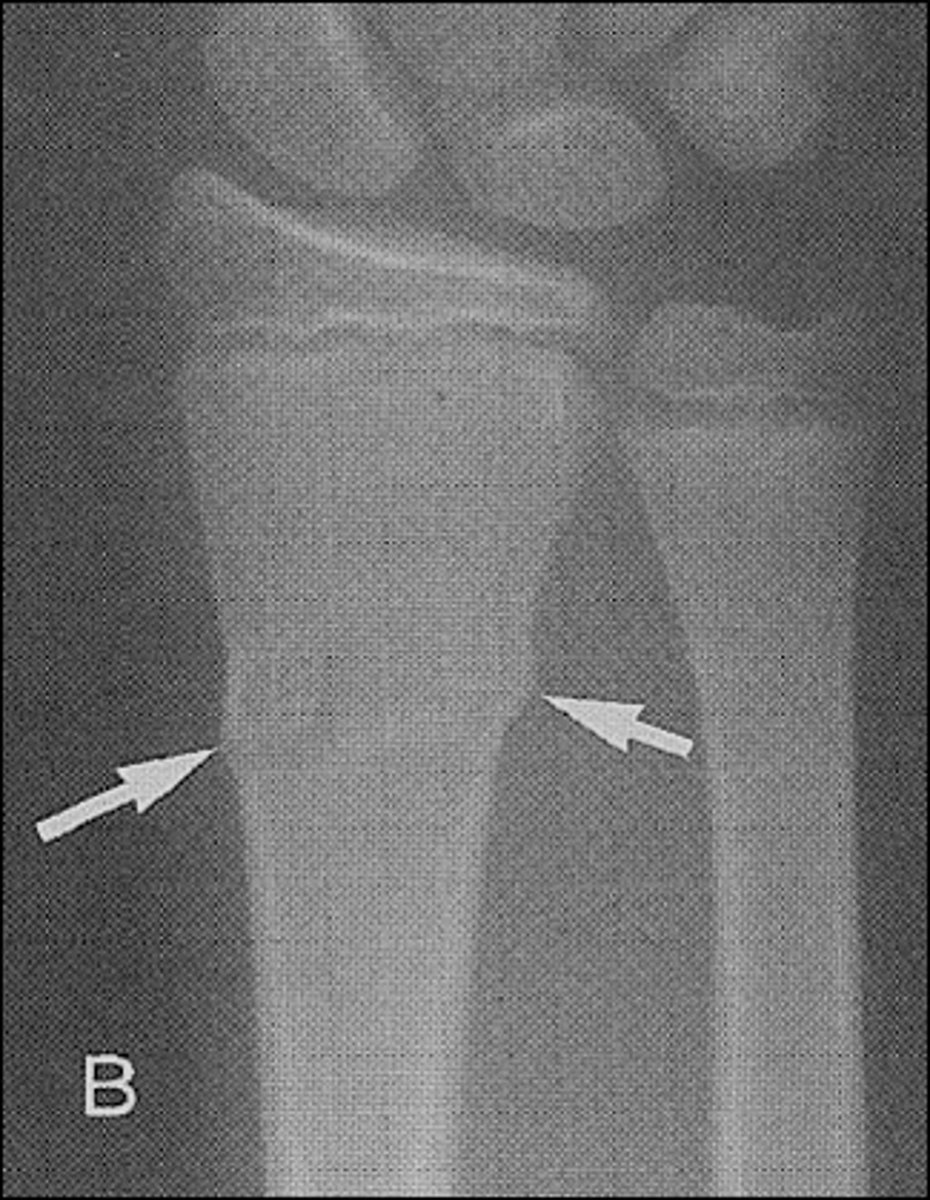

Fracture is nontraumatic in origin, resulted from repeated stress on a bone such as marching or running.

Stress or fatigue fx (march fx)